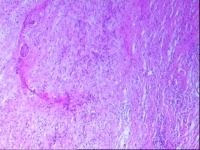

右前臂包块,请教老师,软组织肉瘤?

一般病史2年前发现右前臂多个包块,质软,与周围组织界限较清。

标本名称右前臂包块

大体所见椭圆形包块4枚,直径分别为4.5;1.8;1;0.8CM。表面灰白色,包膜完整,切面灰黄色,质脆。

考虑低度恶性梭形细胞肿瘤,建议IHC标记鉴别:神经,纤维肉瘤,多形性肉瘤。

图2是菊形团样结构?做免疫组化了吗?